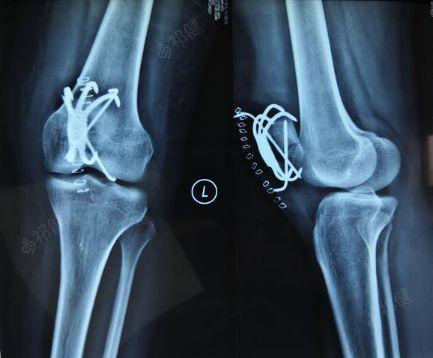

54岁髌骨粉碎性骨折髌骨爪克氏针联合内固定手术一例

左髌骨骨折术后内固定存留取出

固原福利医院病例分享—左髌骨骨折

一例左侧膑骨骨折病例